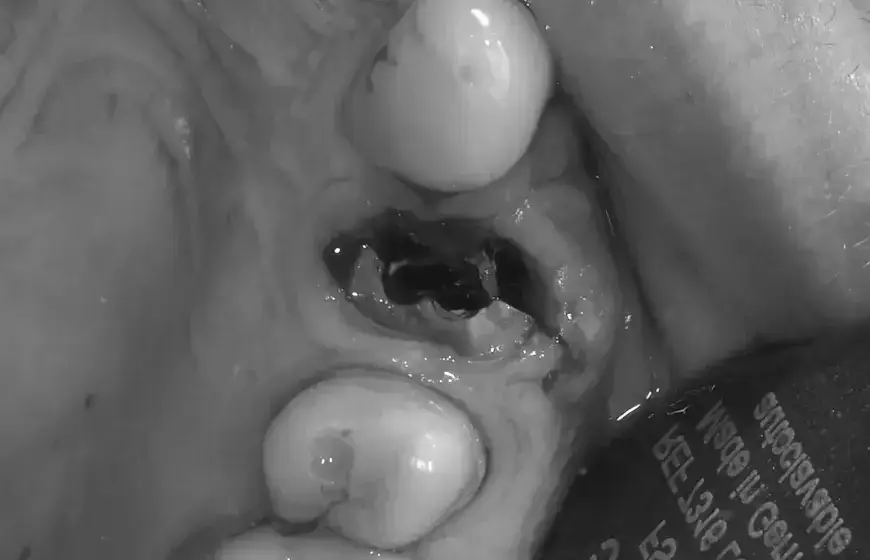

Suchy zębodół bolesne powikłanie, którego chcesz uniknąć za wszelką cenę

Suchy zębodół, czyli alveolitis sicca, to jedno z najbardziej bolesnych powikłań po ekstrakcji zęba. Dochodzi do niego, gdy skrzep krwi zostanie wypłukany lub rozpuści się przedwcześnie, pozostawiając odsłoniętą kość zębodołu. Objawy to zazwyczaj silny, pulsujący ból, który pojawia się 2-3 dni po zabiegu i promieniuje do ucha, skroni lub szyi. Często towarzyszy mu nieprzyjemny zapach z ust i gorączkowanie. Zbyt wczesne lub zbyt energiczne płukanie, a także palenie papierosów czy picie przez słomkę, to główne czynniki ryzyka. W moim gabinecie zawsze podkreślam, że lepiej dmuchać na zimne i unikać wszystkiego, co mogłoby naruszyć skrzep, niż później zmagać się z tym niezwykle nieprzyjemnym stanem.